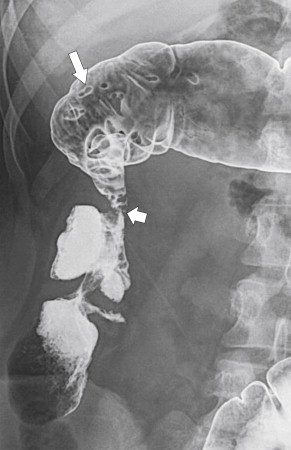

The imaging features are similar to those described in the small bowel, although the imaging of colonic Crohn disease can, at times, mimic those of UC. However, there are a number of distinguishing features that help to differentiate the two diseases ( Table 5-3 ). Plain radiography may demonstrate mucosal thickening ( Fig. 5-19 ) or toxic megacolon. Contrast enema studies (usually barium) may demonstrate involvement of the whole colon (which is therefore difficult to distinguish from UC), but this is uncommon. More commonly a variable segment of the colon is affected ( Fig. 5-20 , A ), and the disease may or may not involve the rectum. Acute disease at CT may present with mural stratification similar to that in the small bowel, representing mucosal and serosal hyperemia with submucosal inflammation or simple mural thickening and mesenteric edema ( Fig. 5-20 , B ). Aphthous ulceration is characteristic of Crohn disease ( Fig. 5-21 ). As in the small bowel, the mucosa in active disease enhances avidly after the administration of IV gadolinium. Although CT is easier and faster to perform, many patients with Crohn disease are young and may require repetitive assessment of the extent of their disease, so avoiding the radiation dose from multiple CT images is preferable. Therefore MRI is often advised, and newer MR enterographic techniques, particularly of the small bowel, have proved highly effective for evaluating the extent of disease ( Fig. 5-22 ). Furthermore, the extent of perianal disease is best imaged with MRI, which can outline the relationship of inflammatory disease to the internal and external anal sphincters; this is important to determine whether surgical repair is needed.

Figure 5-20, A, BE in a 33-year-old man with focal left-sided Crohn disease with spiculated mucosal changes from acute disease ( arrow ). B, Coronal contrast-enhanced CT in a 44-year-old woman with prior surgery for Crohn disease ( arrow ) and now acute disease in the ascending colon ( arrowhead ) with wall thickening and mucosal and mesenteric hyperemia ( small arrow ).